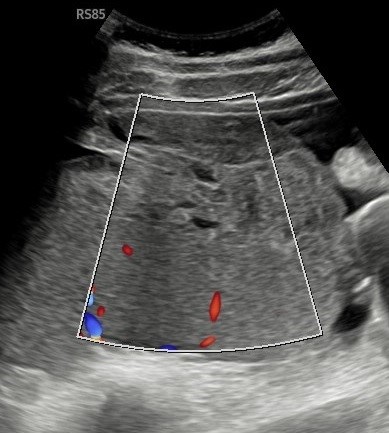

B Mode ultrasound findings confirmed hepatosplenomegaly along with a small volume of free fluid.

Figure 1 above Ultrasound confirms splenomegaly with a small volume of free fluid(arrow).